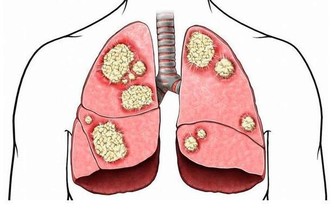

2.增加患病風險睡眠障礙問題以及慢性睡眠不足可增加你患有這些疾病的風險:

心臟疾病,心臟病發作,心臟衰竭,心律不齊,高血壓,中風,糖尿病。據估計,

有九成失眠患者(以難入睡和易醒為特點的人群)還伴有其它一些健康問題。